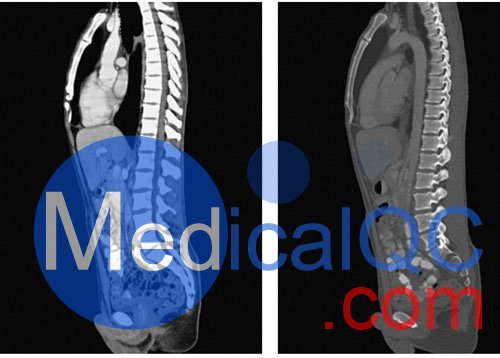

WEK57-01門靜脈期軀干模體,WEK57-01軀干模型模擬了門靜脈期的造影劑增強胸部、腹部和骨盆。它覆蓋了會陰的第二胸椎。

右側(cè)有髂淋巴結(jié)腫塊。

真實模擬脈管系統(tǒng)、骨骼和軟組織,包括肺、心臟、肝臟、膽囊、胰腺、脾臟、腎上腺、腎臟、胃、小腸、結(jié)腸、膀胱和前列腺。

右側(cè)髂外淋巴結(jié)腫塊。

WEK57-01門靜脈期軀干模體,WEK57-01軀干模型成像效果圖: